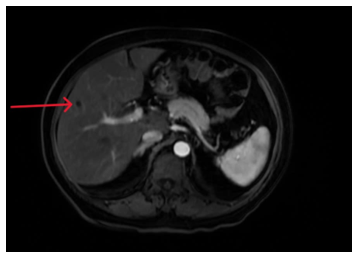

- Chụp MRI ổ bụng có tiêm thuốc đối quang từ: Gan kích thước bình thường, bờ đều. Nhu mô gan có vài nang đường kính 5mm, không thấy bất thường cấu trúc và tín hiệu.

Hình 4: Chụp MRI ổ bụng có hình ảnh nang gan (mũi tên)